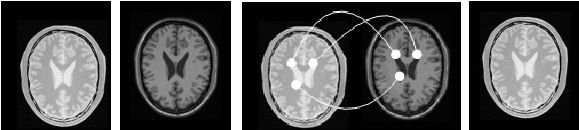

图象配准是图象融合的前提,是公认难度较大的图象处理技术,也是决定医学图象融合技术发展的关键技术。在临床诊断中,单一模态的图像往往不能提供医生所需要的足够信息,常需将多种模式或同一模式的多次成像通过配准融合来实现感兴趣区的信息互补。在一幅图像上同时表达来自多种成像源的信息,医生就能做出更加准确的诊断或制定出更加合适的治疗方法[16]。医学图像配准包括图像的定位和转换,即通过寻找一种空间变换使两幅图像对应点达到空间位置和解剖结构上的完全一致。图6简单说明了二维图像配准的概念。图(a)和图(b)是对应于同一人脑同一位置的两幅 MRI 图像,其中图(a)是质子密度加权成像,图(b)是纵向弛豫加权成像。这两幅图像有明显的不同,第一是方位上的差异,即图(a)相对于图(b)沿水平和垂直方向分别进行了平移;第二是两幅图像所表达的内容是不一致的,图(a)表达不同组织质子含量的差别,而图(b)则突出不同组织纵向弛豫的差别。图(c)给出了两幅图像之间像素点的对应映射关系,即(a)中的每一个点fx都被映射到(b)中唯一的一个点rx。如果这种映射是一一对应的,即一幅图像空间中的每一个点在另外一幅图像空间中都有对应点,或者至少在医疗诊断上感兴趣的那些点能够准确或近似准确的对应起来,我们就称之为配准[17,18]。图(d)给出了图(a)相对于图(b)的配准图像。从图(d)中可以看出,图(d)与(b)之间的的像素点的空间位置已经近似一致了。1993 年 Petra 等综述了二维图像的配准方法,并根据配准基准的特性,将图像配准的方法分为基于外部特征的图象配准(有框架) 和基于图象内部特征的图象配准(无框架) 两种方法。 后者由于其无创性和可回溯性, 已成为配准算法的研究中心。

(a)                 (b)                                (c)                           (d)

图8 医学图像配准原理